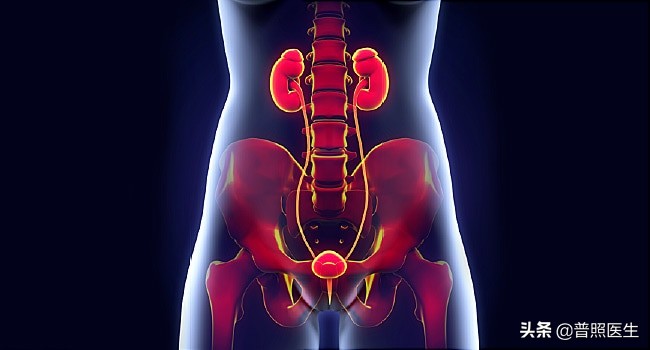

讲表现之前,我们首先弄清楚一个概念:尿路从上到下分别包括:肾脏、输尿管、膀胱和尿道。上尿路指肾脏和输尿管,下尿路指膀胱和尿道。

尿路从上到下分别包括:肾脏、输尿管、膀胱和尿道。